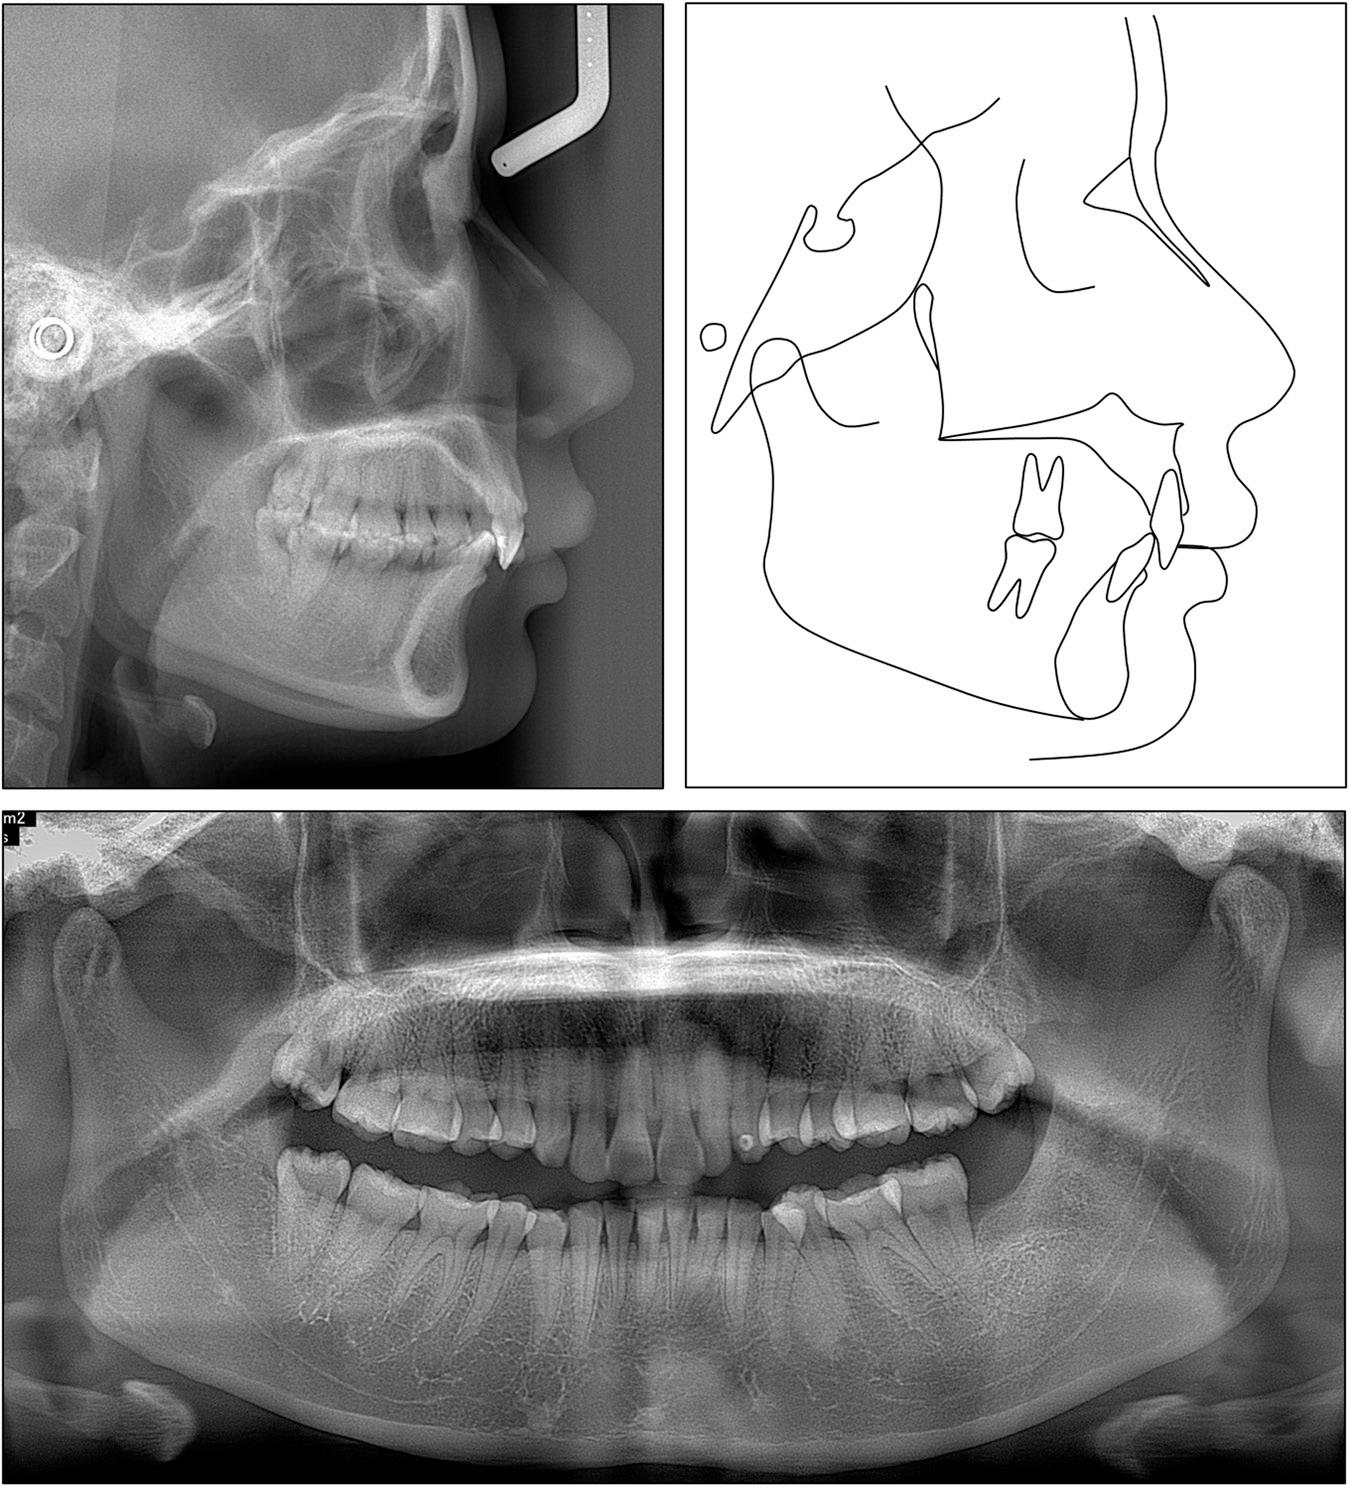

Cephalometric measurements

| Pretreatment | Posttreatment | |

|---|---|---|

| Skeletal | ||

| SNA (°) | 85.7 | 84.8 |

| SNB (°) | 79.6 | 80.1 |

| ANB (°) | 6.1 | 4.7 |

| FMA (°) | 20.0 | 20.5 |

| Dental | ||

| U1-SN (°) | 80.3 | 92.4 |

| U1-PP (°) | 89.2 | 101.1 |

| U1-NA (°) | -5.5 | 7.6 |

| U1-NA (mm) | -3.4 | -1.2 |

| IMPA (°) | 94.2 | 95.1 |

| L1-NB (°) | 22.1 | 22.7 |

| L1-NB (mm) | 2.8 | 3.1 |

| Interincisal angle (°) | 157.3 | 144.9 |

| Upper incisal display (mm) | 5.8 | 3.8 |

| Soft tissue | ||

| E-line/UL (mm) | -0.7 | -0.9 |

| E-line/LL (mm) | -1.2 | -1.2 |